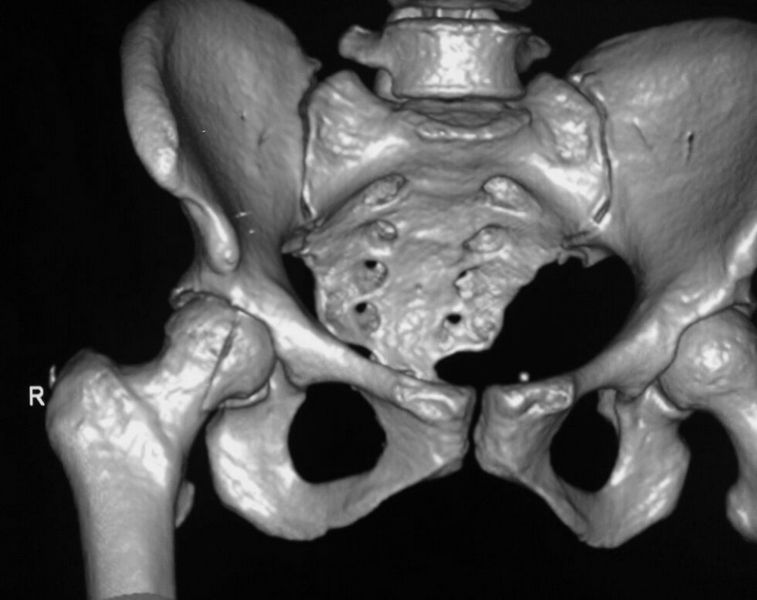

При поступлении выполнено закрытое вправление головки бедра, налажено скелетное вытяжение. Контрольный рентген показал разницу в ширине суставных щелей в сравнении с неповрежденной стороной. Сделали КТ, которое подтвердило наличие внутрисуставного фрагмента задней стенки вертлужной впадины и перелом нижне-медиального сегмента головки со смещением (Pipkin IV).

Через 12 дней выполнен остеосинтез головки 3-мя самокомпрессирующими винтами Герберта. Доступ Kocher-Langenbeck с флип-остеотомией большого вертела и задним хирургическим вывихом головки бедра. Интерпонирующий внутрисуставной фрагмент представлял собой лабрум с тонкой костной пластинкой от заднего края впадины. Фрагмент извлечен и фиксирован техникой spring-plate.

1. Как раз для таких маленьких фрагментов и показана техника spring-plate, где невозвожно провести стягивающий винт. Размера "крючков" на такой пластинке едва хватает на удержание фрагмента, конфликта с головкой нет. На АО Foundation такая методика называется "spring hook plate". Роль второй пластины сводится к удержанию spring-plate от смещения.